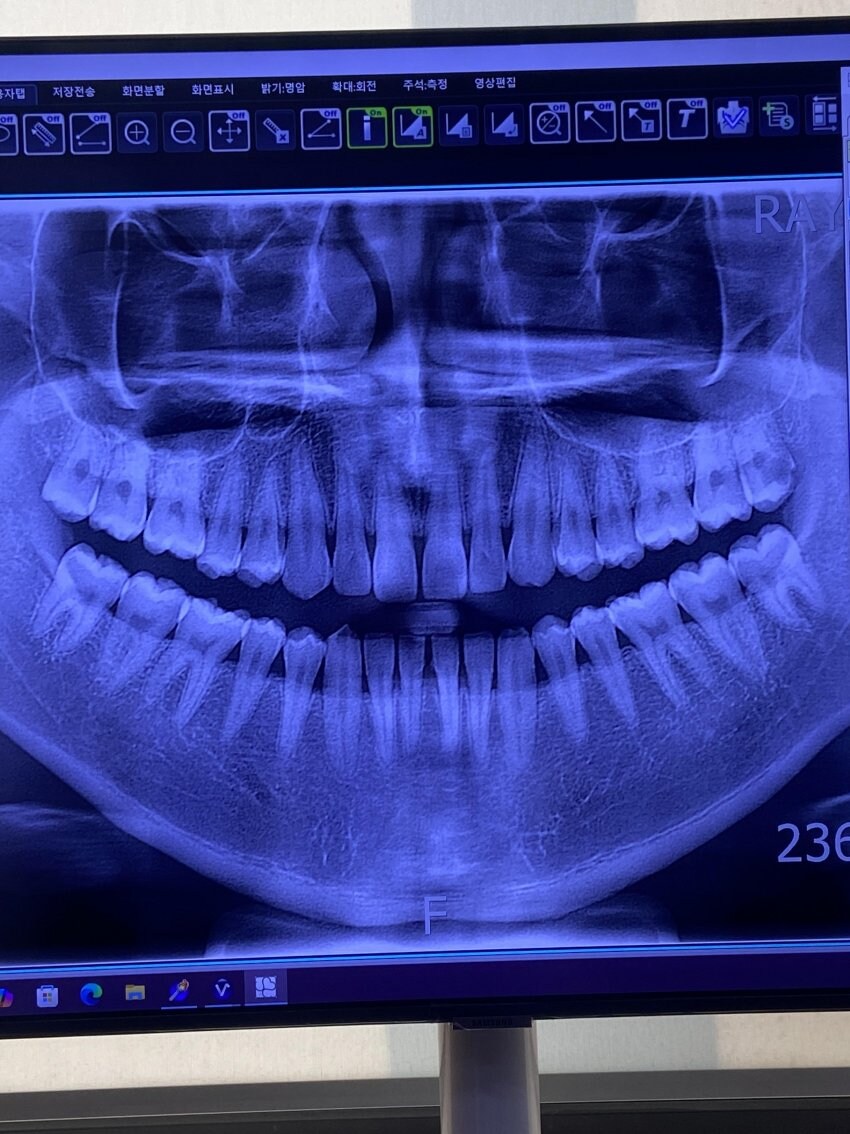

축복받은 치열 Anonymous | 2025.10.26 02:39 | 조회 5 https://qquing.net/bbs/board.php?bo_table=humor&wr_id=1678759 주소 복사 이전글 다음글 랜덤 만화 목록 본문 오오... 추천 0 비추천 0